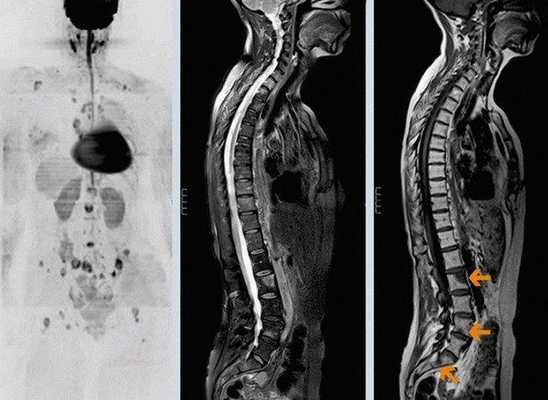

Метастазы. Любая злокачественная опухоль может метастазировать в костную ткань, но наиболее вероятно распространение из следующих органов: молочная железа, предстательная железа, почки, щитовидная железа, и легкие. Гематогенное метастазирование может идти двумя путями по венозной системе или по артериальной системе. У позвоночника и его окружающих тканей хорошее кровоснабжение, причем с дренированием многих структур области малого таза через венозную систему называемую сплетением Бэтсона. Лимфатические каналы тоже могут быть путем метастазирования, но лишь в трети случаев. Распространение или метастазы опухолей откуда-либо из тела в позвоночник возможно после длительного периода роста опухоли в первичном очаге. Метастатические опухоли, как правило, сопровождаются выраженным болевым синдромом. Если метастатическая опухоль достаточно большая, то возможно компрессионное воздействие на спинной мозг, что может проявляться нарушением проводимости моторных функций конечностей, нарушениям функции кишечника и мочевого пузыря. Как правило, метастатический рак не излечим, и задача лечения направлена на уменьшение болевого синдрома и декомпрессию невральных структур (оперативными методами) и, таким образом, сохранение качества жизни пациента в максимально возможной степени. Хирургия, химиотерапия, и дозированная радиационная терапия помогают уменьшить боль при метастатическом поражении позвоночника.

В спинной мозг чаще метастазируют опухоли молочной железы (21 %), лёгких (19 %), простаты (7,5 %), почек (5 %), желудочно-кишечного тракта (4,5 %) и щитовидной железы (2,5 %) [16] .

- метастазы (лимфома, саркома, рак лёгкого, предстательной железы, почек, меланома).

7. Сцинтиграфия. В организм вводят радиоактивные изотопы и по излучению от них получают двумерное изображение. Методом определяют распространение опухоли и количество метастатических очагов [9] .

Метастатические опухоли позвоночника является наиболее распространенными для костных метастазов.

Наиболее распространенными солидными опухолями, вторично поражающими позвоночник являются: рак груди, простаты и почечная карцинома, на которые приходится почти 80% метастазов в позвоночник. На опухоли неизвестного первичного генеза приходится около 5% -10% случаев. Метастазы новообразований кроветворной системы составляют около 4% -10%.